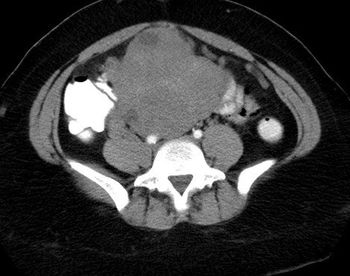

afe abdominal entry and prevention of retroperitoneal vascular injuries during laparoscopic surgery are the ultimate goals of any laparoscopic surgeon. Dr. Linda Nicoll and colleagues very capably have been able to describe a new technique and technology that prevent almost all retroperitoneal vascular injuries during laparoscopic entry.